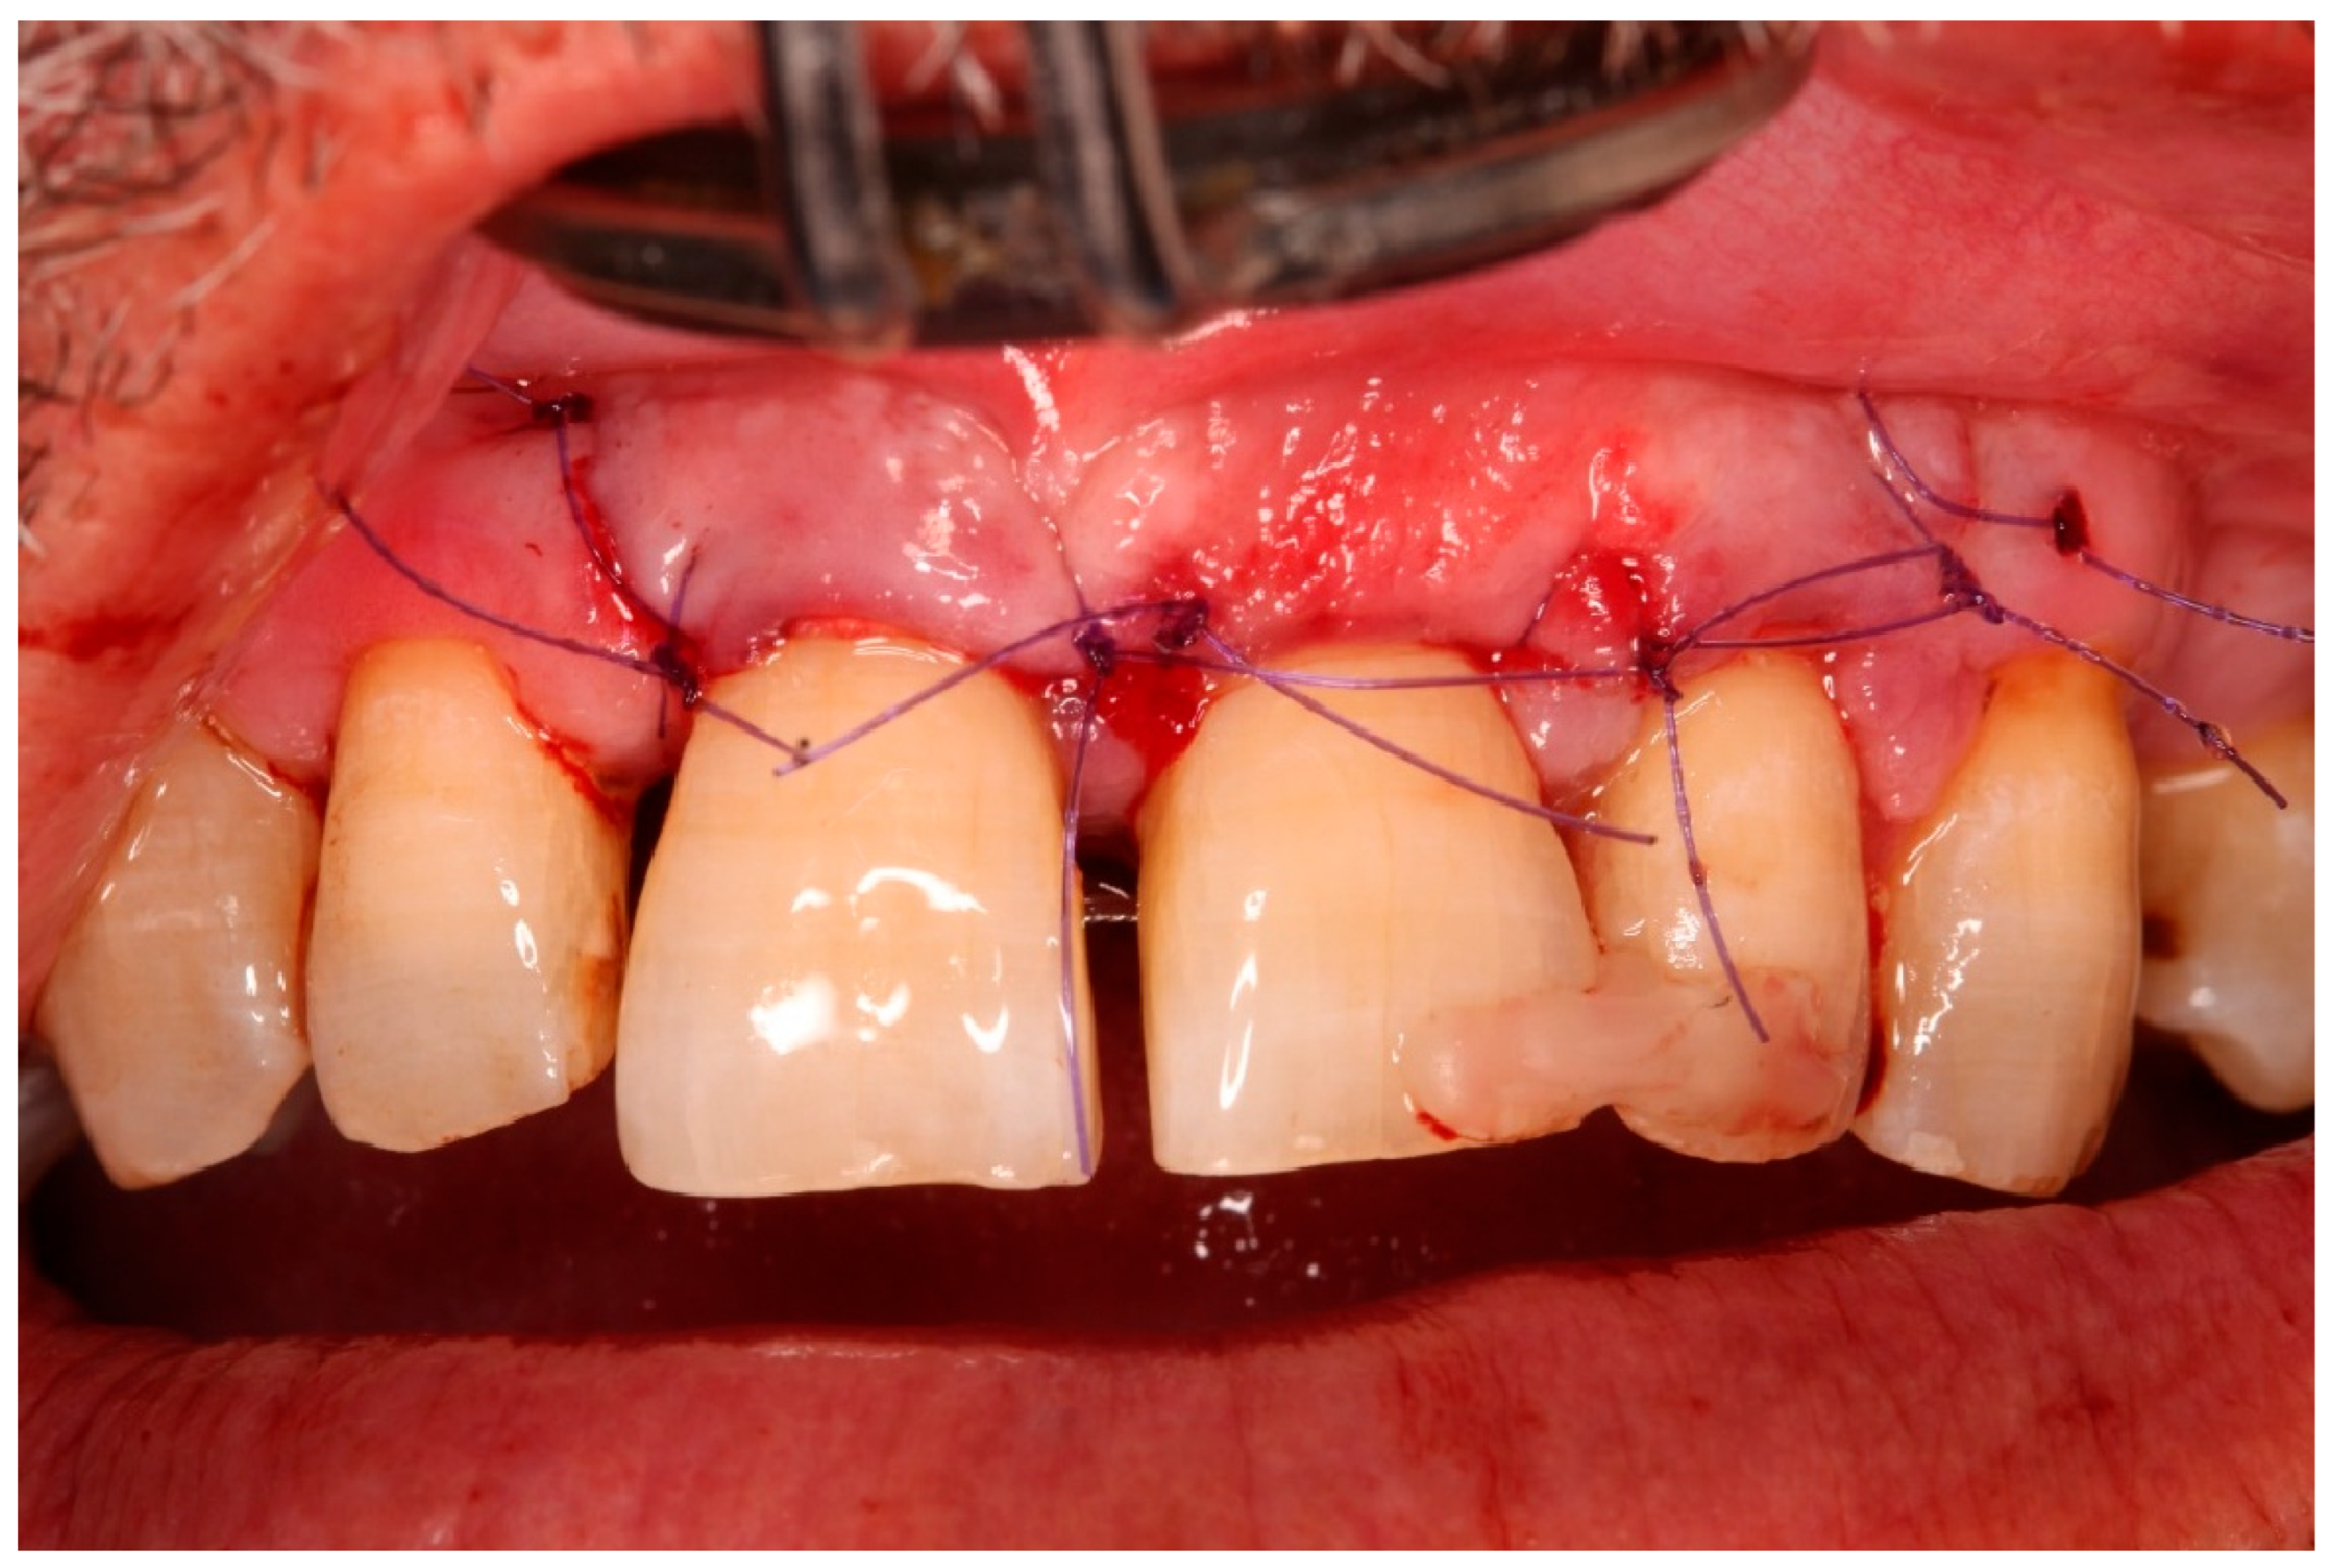

- Replantation and splinting: The original tooth was replanted into the digitally prepared socket, achieving primary stability by adapting to the prepared walls and remaining palatal bone. A semi-rigid splint was placed using fibre-reinforced composite bonded to adjacent teeth, planned for a 4-month period.

- Guided tissue regeneration: A full-thickness flap was elevated to expose the defect morphology. Autologous bone chips collected during drilling were combined with xenograft particles (Bio-Oss®, Geistlich Pharma, Wolhusen, Switzerland) and enamel matrix derivative (Emdogain®, Straumann, Basel, Switzerland) and placed around the replanted root. A resorbable collagen membrane (Bio-Gide®, Geistlich Pharma, Wolhusen, Switzerland) was positioned to stabilize the grafted area and support space maintenance. The flap was repositioned and sutured to achieve primary closure.